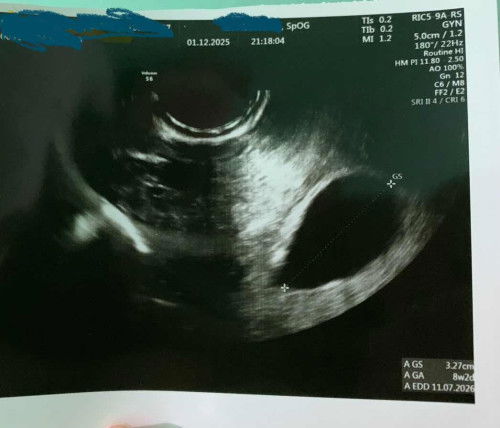

Bun saya sering naik motor ke tempt kerja jaraknya 7 kiloan. Kemrin aku jg plng kampung bawa anak ke neneknya, dan jaraknya sekitar 40 kiloan . Semalam perut aku perih bun. Tapi tenang aja ttp berpikir posif aja, dan tadi subuh kluar flek. Dan paginya aku kmbli lagi ke tempat kontrakan dan lanjut le tempat kerja. Pas pulang siangnya ngeflek lagi bun. Apakah ini aman saja?? #mohonbantujawabbunda #Sharingdong_Bund #bantujawab #sharing